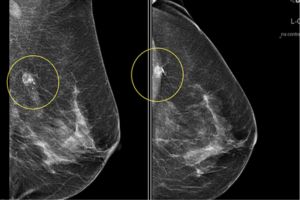

ماموگرافی دیجیتال برای غربالگری، تشخیص زودهنگام و انجام مارکرگذاری دقیق ضایعات پستان